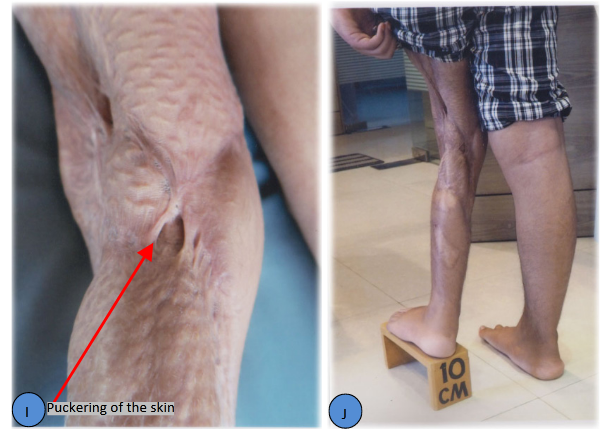

Figure 1 A-J 14 years old boy, Post Traumatic Genu Valgum with Valgus Deformity of left Lower Femur and Upper Tibia Valgus and Procurvatum Deformity with 10cm L. L. D and Puckering of Skin around Knee with Bad Scar.

Everything must be done gradually. In Ilizarov technique gradual distraction is always preferred when amount of deformity is large and bone lengthening is necessary. Here the skin is very bad with bad scar and puckering is obvious.6,7